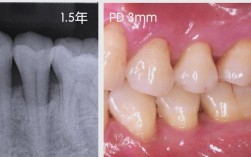

拔大牙前,医生需进行全面评估,以确定手术可行性和风险,首先进行口腔检查,通过视诊观察牙齿龋坏程度、牙龈状况及邻牙关系,用探针检查龋洞深度,牙周探针测量牙周袋深度(判断是否有牙周病);通过叩诊检查牙齿是否有明显疼痛,判断根尖周炎症情况,拍摄X光片(通常包括全景片和根尖片),明确牙根数量、形态、弯曲度,以及牙根与牙槽骨、上颌窦、下颌神经管等重要解剖结构的位置关系,避免术中损伤。